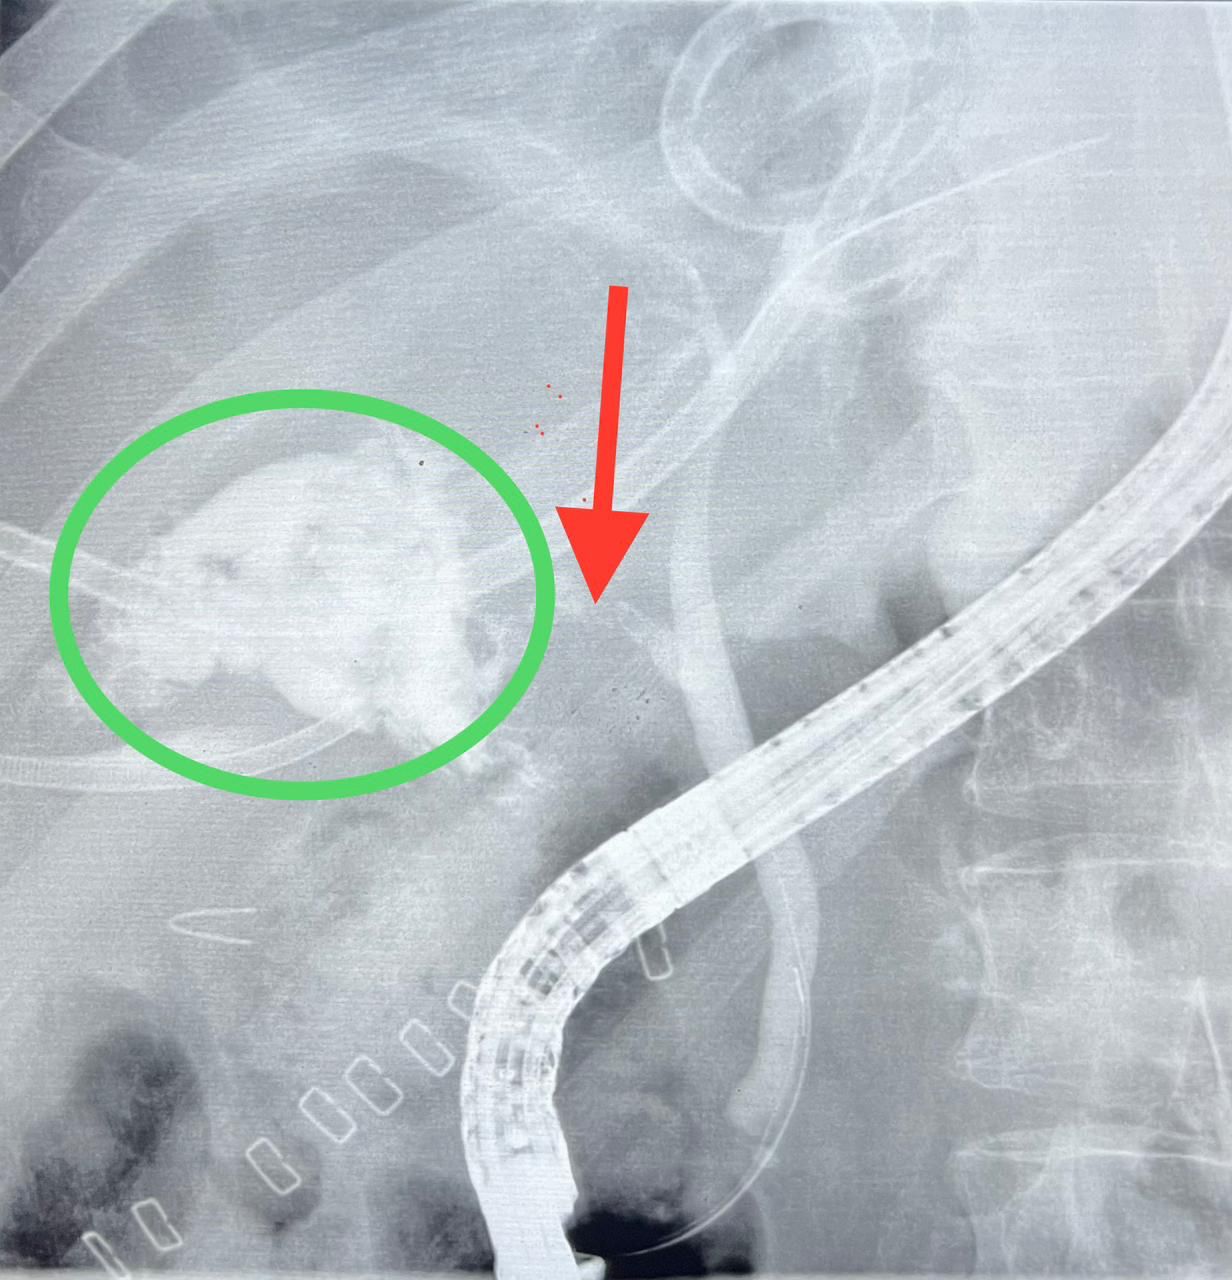

وبينت ” الوزارة ” أن بعد اطلاع الفريق الطبي على كافة الفحوصات والتقارير الطبية للمريض قرر الجهاز الطبي إجراء عملية منظار مجهري للقنوات المرارية الكبدية ، حيث كان يعاني المريض من مرارة ملتهبه مع غرغرينا ، بالاضافة لإلتهاب حول الكبد وتسمم دموي.

وأوضحت ” الصحة ” ان الفريق الطبي قد أجرى منظار مجهري للقنوات الصفراوية تحت تخدير عام وبإستخدام الأشعة ، وتم فتح صمّام القناة الصفراوية ، وزرع دعامة بلاستيكية لسد منطقة التسريب بنجاح دون حدوث أي مضاعفات.